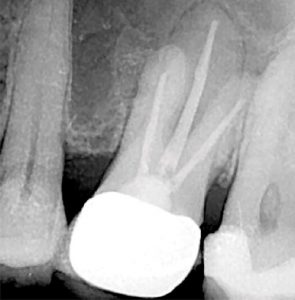

A two-dimensional intraoral radiograph revealed a prior history of root canal therapy and a porcelain-fused-to-metal (PFM) crown (both completed approximately 10years ago) (Figure 2).

After debridement and shaping, Ca(OH)2 (Ultrocal XS) was placed in the root canal space to further enhance disinfection. Prior to obturation, drainage was noted coming from the MB2 canal; drainage was arrested and the canals root was filled with vertical condensation of warm gutta percha (VCWG) and AH-Plus sealer (Figure 3)